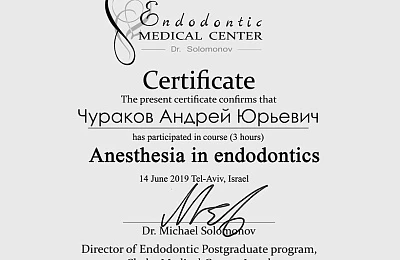

Сертификаты и лицензии

Повышение квалификации